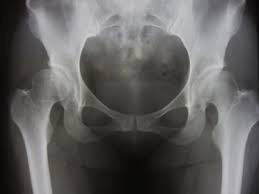

② X선 검사

고관절의 뼈 구조, 관절 간격, 골절 유무 등을 확인하는 기본적인 영상 검사입니다.